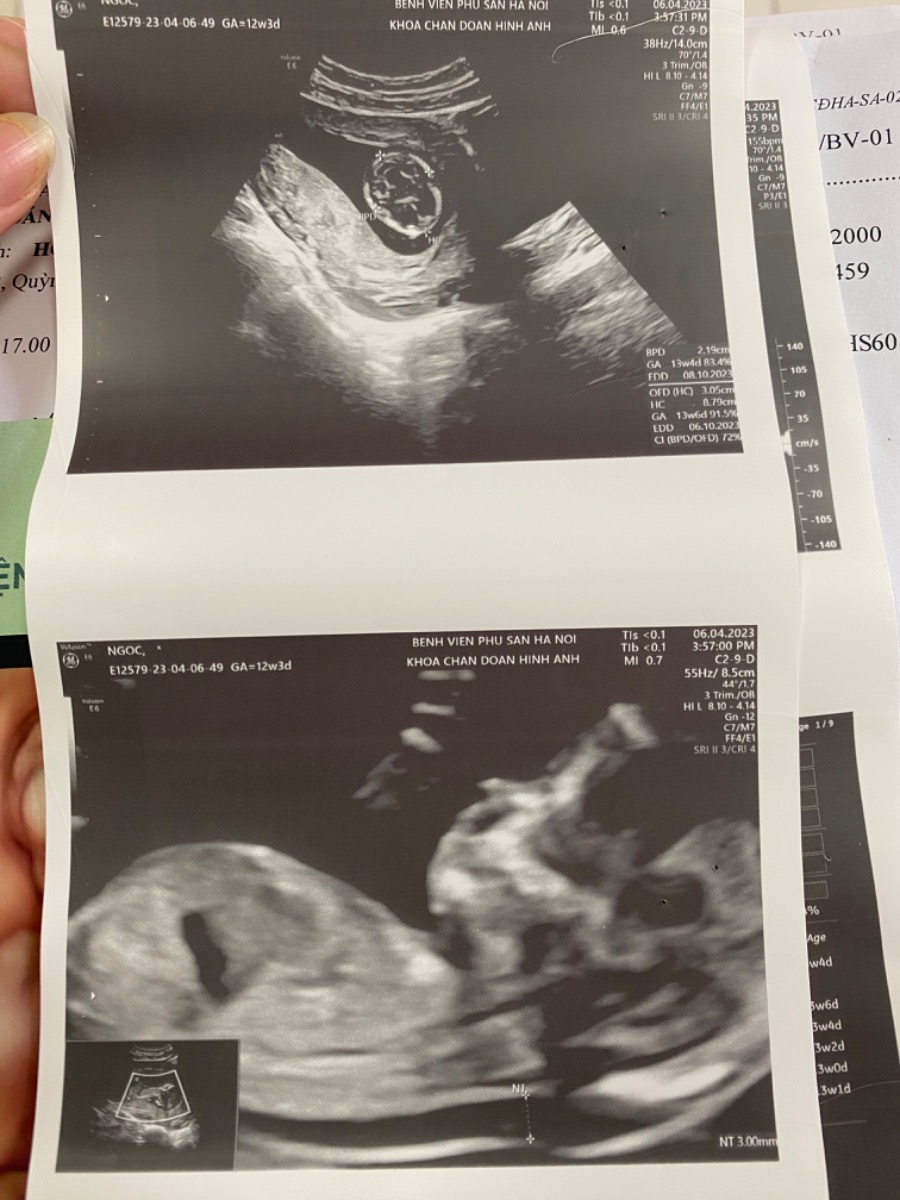

Nếu thai nhi 13 tuần tuổi thì siêu âm thai đo độ mờ da gáy thường sẽ nhỏ hơn 2,8mm. Nhưng nếu độ mờ da gáy TRÊN 3mm, nguy cơ thai nhi mắc hội chứng Down là khá cao.

Tuy nhiên kết quả kiểm tra độ mờ da gáy chỉ giúp bác sĩ phán đoán được 75% nguy cơ trẻ bị Down. Hơn nữa, nếu chỉ dựa vào một chỉ số duy nhất là độ mờ da gáy thì không thể kết luận được gì.

Sau khi khám trực tiếp cho mom và dựa vào tất cả các chỉ số, bác sĩ sẽ có chỉ định phù hợp. Trong những trường hợp có nguy cơ, bác sĩ có thể chỉ định làm các xét nghiệm chuyên sâu hơn như sinh thiết nhung mao màng đệm hay chọc ối. Mom hãy làm theo các hướng dẫn của bác sĩ nhé!